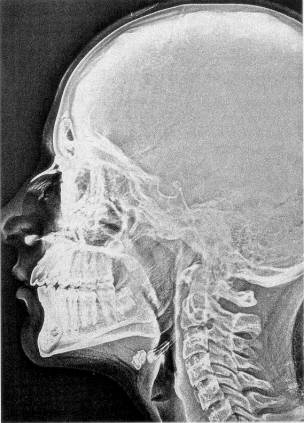

La tomografia computerizzata è una tecnica radiologica relativamente recente destinata ad esaminare le strutture interne del corpo a livello macroscopico senza effetto oscuramento dovuto al sovrapporsi delle strutture, rendendo superfluo l’uso di mezzi di contrasto. Contrariamente alla radiologia tradizionale, di cui si riporta un esempio in fig. 1‑1, è in grado di risolvere le piccole differenze di contrasto tra strutture vicine di densità simile (es. parti molli).

Figura 1‑1 Immagine radiografica tradizionale